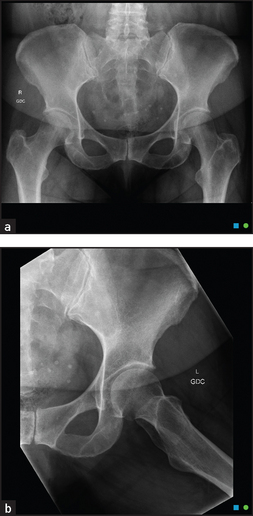

The hip is a ball-and-socket synovial joint (see Figure 24.30). The socket is formed by three bones: the ilium, the ischium and the pubis. The ball is the head of the femur. Surrounding tendons and nerves may cause symptoms that need to be distinguished from hip abnormalities.

In patients with osteoarthritis of the joint, internal rotation, abduction and extension are usually restricted.8 Osteoarthritic joints show loss of joint space, sclerosis (thickening and increased radiodensity) at the joint margins and osteophyte (bony outgrowth) formation on plain X-ray films.